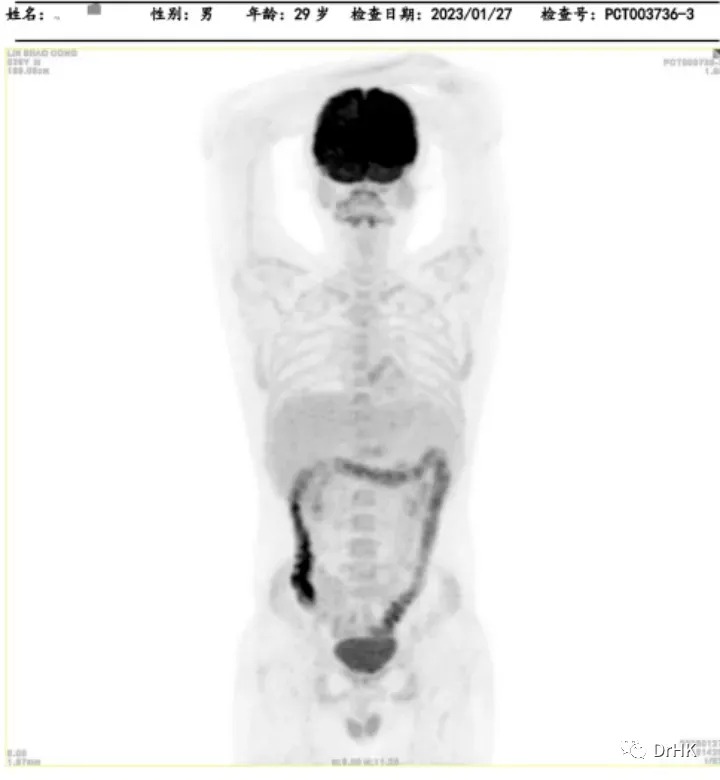

PET-CT

Deauville score: 5 points

Liver involvement: A lesion measuring approximately 3.2×2.6×3.7 cm, with a maximum SUV value of 22.4

Brain: Slightly low-density areas in the deep right temporal lobe and basal ganglia, suggesting lymphoma involvement based on MRI images

Multiple bone lesions: Bone absorption and destruction changes in multiple sites including the bilateral scapulae, clavicles, ribs, sternum, pelvic bones, and vertebrae. Some areas showed increased bone density, with the left iliac bone being the most prominent

Left gluteus maximus muscle: A lesion measuring approximately 1.2×1.6×1.5 cm, with a maximum SUV of 12.4

The patient was subsequently followed up regularly, with imaging evaluations completed six months and one year after the transplant. It is gratifying to report that the patient has maintained complete remission throughout this period. The PET images are shown below:

Six-Month Post-Transplant Imaging Evaluation